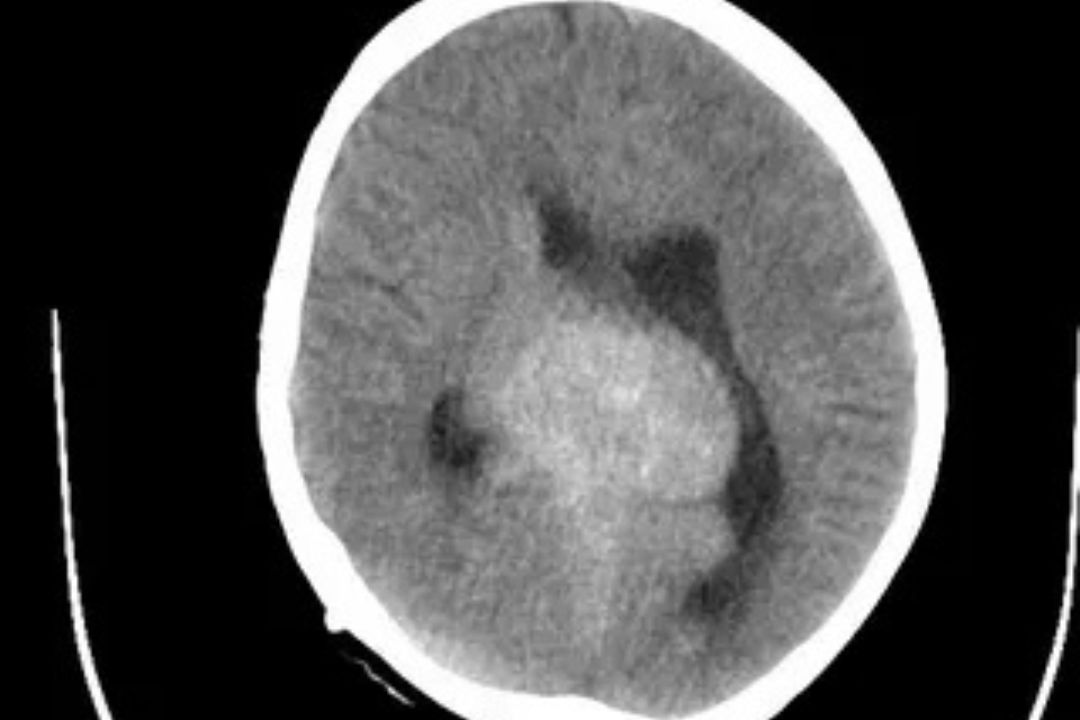

A CT Brain (Plain) scan is a non-contrast computed tomography test used to visualize the brain’s internal structures such as bones, tissues, and blood vessels. It helps doctors detect abnormalities like bleeding, fractures, tumors, and strokes quickly and effectively without the use of contrast dye.

This test uses X-ray imaging combined with computer technology to provide cross-sectional images of the brain. It is often the first and fastest step in emergency neuroimaging.